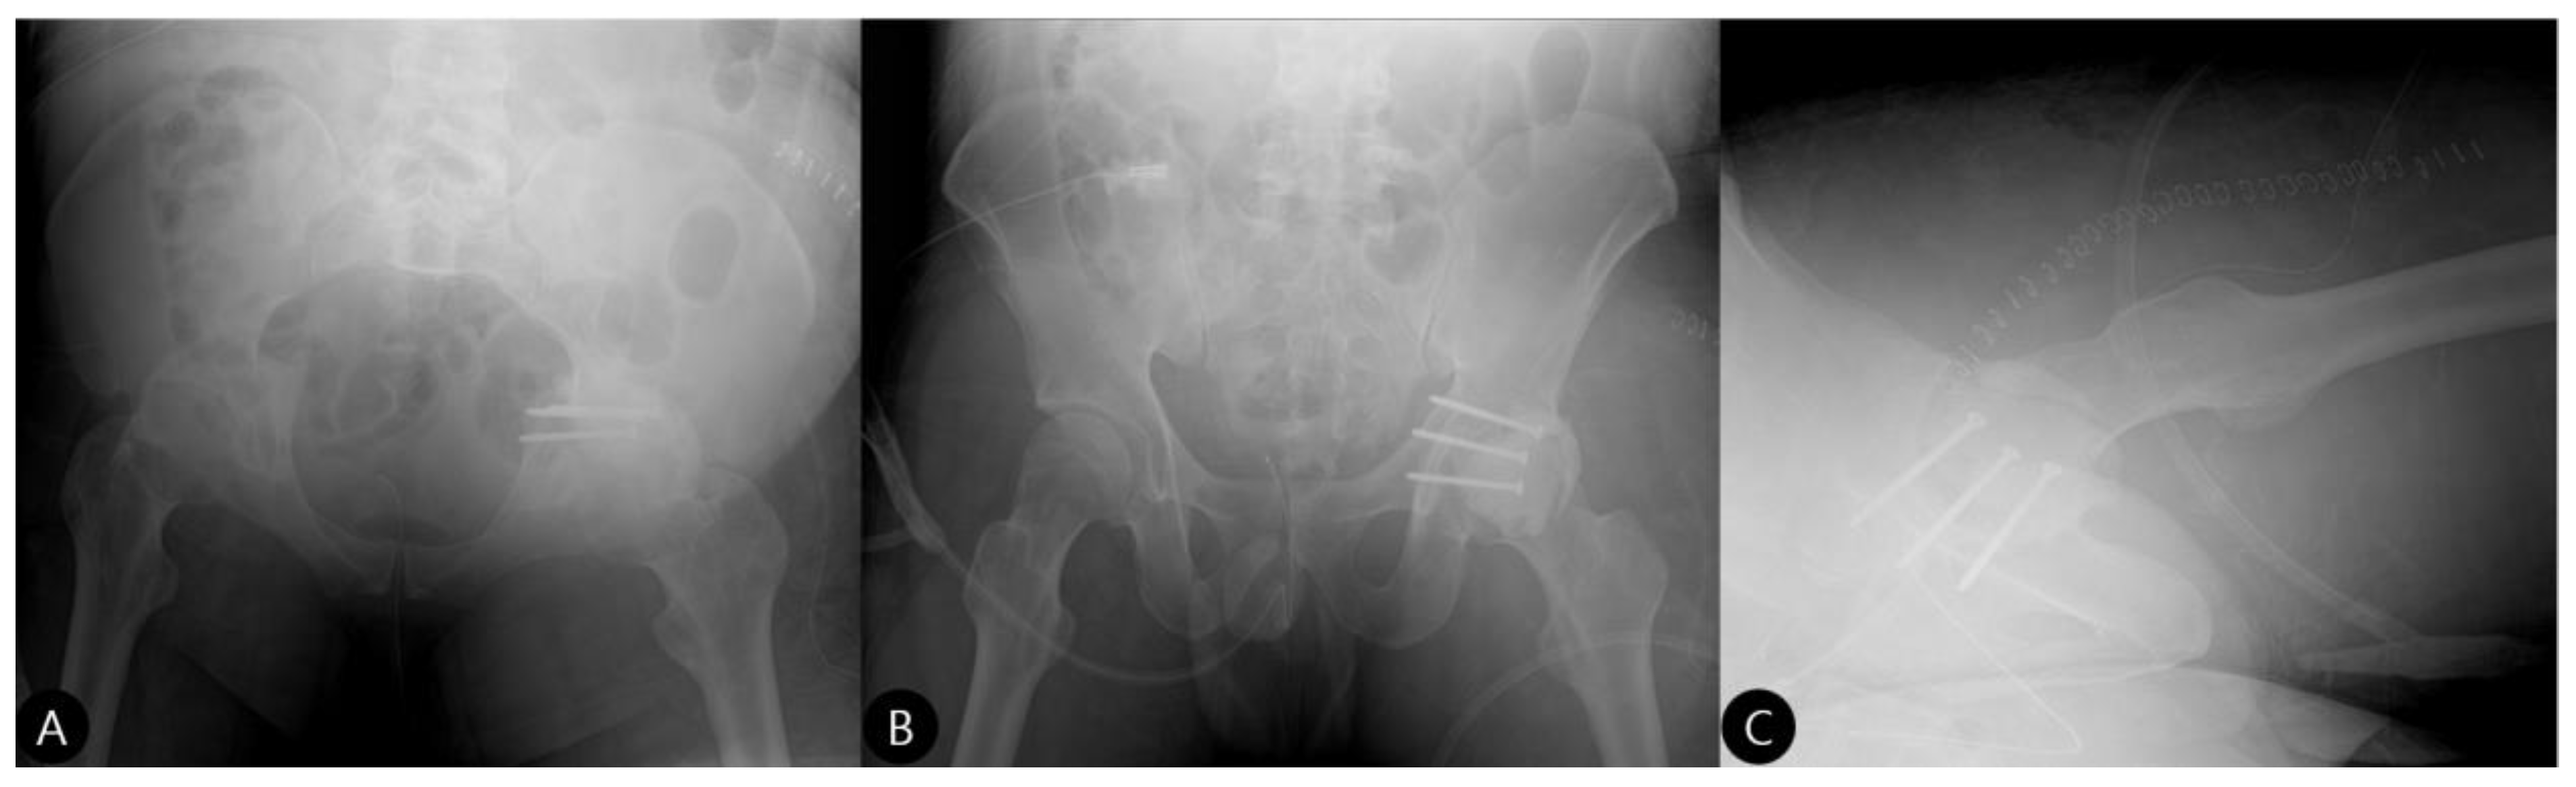

- Reduction and Final Assessment: The hip was reduced under direct vision. Intraoperative fluoroscopy confirmed a concentric reduction, correct implant placement, and the absence of cement fragments in the joint. The stability of the construct was tested through a range of motion. Postoperative imaging confirmed the anatomical reduction and the accurate contouring of the cement construct (Figure 4 and Figure 5).